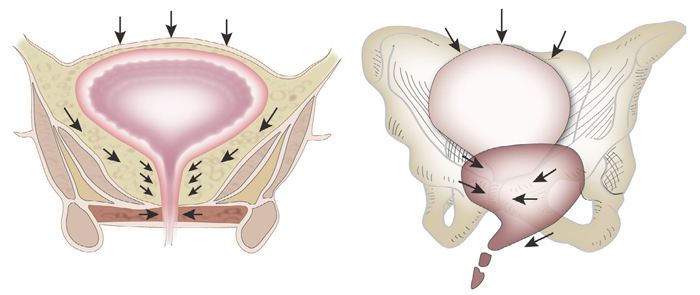

压力性尿失禁是指喷嚏或咳嗽等腹压增高时出现不自主的尿液自尿道外口渗漏。症状表现为咳嗽、喷嚏、大笑等腹压增加时不自主溢尿。体征是腹压增加时,能观测到尿液不自主地从尿道流出。尿动力学检查表现为充盈性膀胱测压时,在腹压增加而无逼尿肌收缩的情况下出现不随意漏尿。

3、盆腔脏器脱垂。压力性尿失禁和盆腔脏器脱垂紧密相关,二者常伴随存在。盆腔脏器脱垂患者盆底支持组织平滑肌纤维变细、排列紊乱、结缔组织纤维化和肌纤维萎缩可能与压力性尿失禁的发生有关。